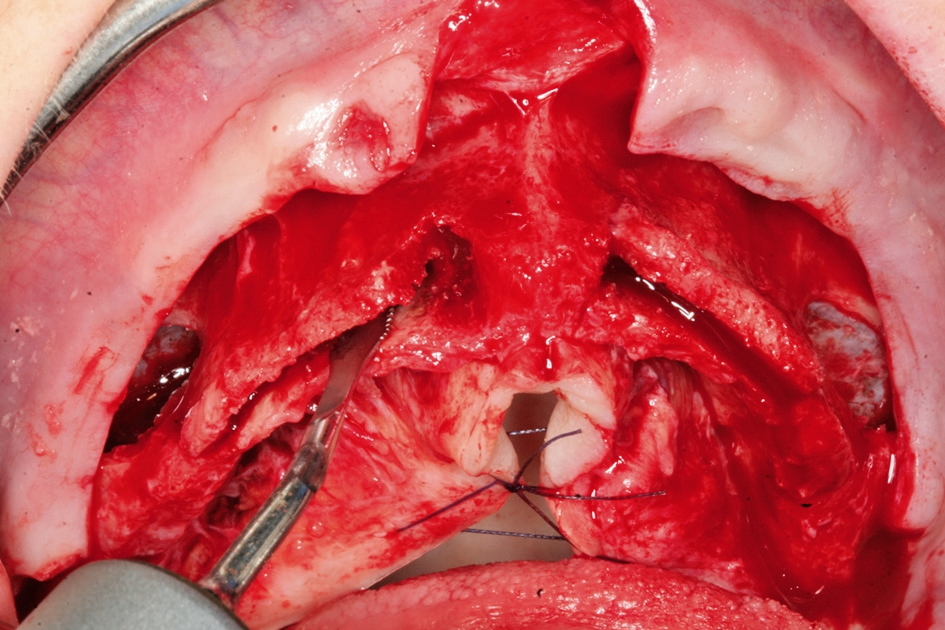

Für eine ausreichende Abdeckung der eingebrachten Implantate jeweils palatinal und vestibulär und Sicherstellung der Nutrition der Knochenlamellen ist eine Mindestbreite des Knochens von 2 bis 3 mm erforderlich. Für die Durchführung des Bone Splittings ist es notwendig, eine relativ tiefe Osteotomie des Kieferkamms zu erreichen. Dies kann heute entweder mit oszillierenden Sägen oder auch mit Hochleistungs- Piezochirurgiegeräten erfolgen [8] (Abb. 3). Bei der Anwendung der Piezochirurgie im Vergleich zur oszillierenden Säge kann die Präparation schonend erfolgen, gerade dann, wenn die Behandlung nicht in Intubationsnarkose erfolgt. Auch bei der Präparation eines Mukoperiostlappens ist es anzustreben, dass es zu keiner kompletten Loslösung des mobilisierten Knochensegmentes kommt. Diese sollte auch in der Basis weiterhin am Knochen fixiert sein und lediglich im Sinne einer Grünholzfraktur mobilisiert werden. Nach der Implantatinsertion wird der Spaltraum mit eventuell anfallenden Knochenspänen und Kollagenfleece oder auch mit einem resorbierbaren Knochenersatzmaterial aufgefüllt. Bei reduziertem vertikalen Knochenangebot im posterioren Bereich und der Notwendigkeit einer Sinusbodenelevation sollte dann die Osteotomielinie für das Bone Splitting nicht fortgeführt werden, da sonst keine ausreichende Primärstabilität für die Implantate erreicht werden kann (Abb. 4).

Durch die Mobilisation der Knochensegmente kann es zu Resorptionsvorgängen kommen. Dies bedeutet beim Bone Splitting den Verlust der vestibulären Lamelle mit einer Dehiszenz und dementsprechend ästhetischen Einbußen bzw. einem erhöhten Risiko einer Periimplantitis. Daher ist es empfehlenswert und durch tierexperimentelle Studien belegt, dass ein Resorptionsschutz am besten dadurch erreicht werden kann, dass neben dem Bone Splitting noch eine weitere Auflagerungsplastik erfolgt, die mit einer Membran abgedeckt wird [2, 7, 17]. Dadurch wird die Osseointegration des Implantates mit einer knöchernen Lamelle abgedeckt, sodass ein hoher Knochen-Implantat-Kontakt erreicht werden kann. Dies bedeutet eine langzeitstabile Versorgungsmöglichkeit der Implantate. Die laterale Augmentation unter der Membrantechnik sichert das Knochengewebe vor einer frühen Resorption, sodass mit einem erhöhten Periimplantitisrisiko nicht zu rechnen ist [2] (Abb. 5 und 6).